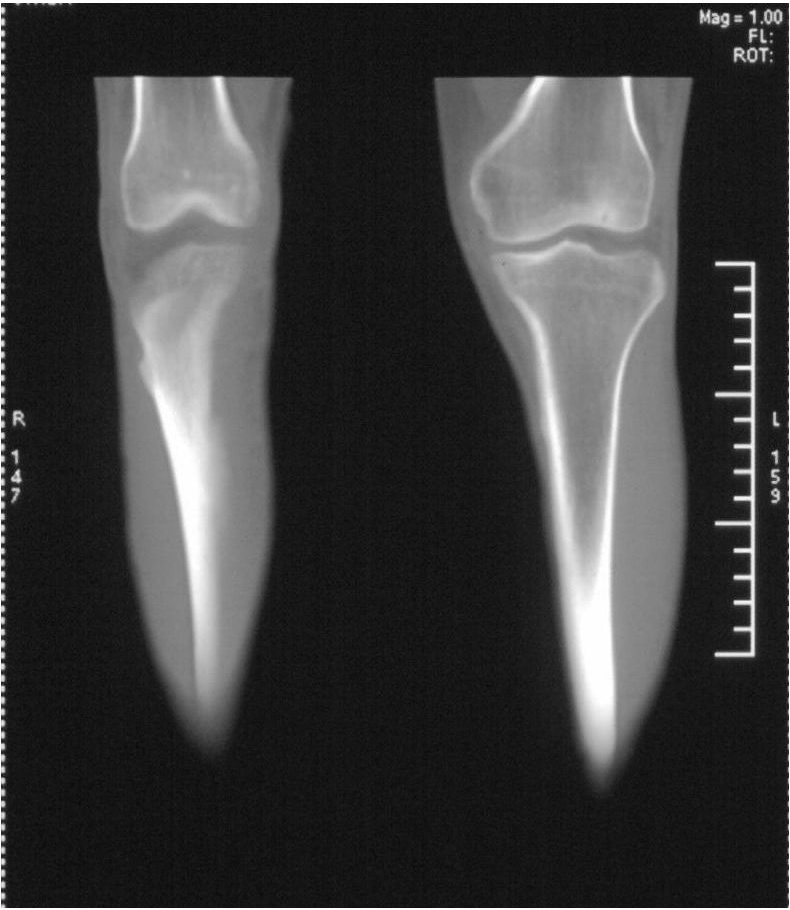

男,42岁。4个月前钢筋钝伤右侧小腿部,当时因无明显外伤,未引起重视。一周后因受伤腿部疼痛,发现肿胀,随后到当地医院进行检查(2008年4月16日)。因未发现骨质异常未引起重视,仅仅进行口服抗生素治疗处理。经过一段时间治疗但未见明显治疗效果在5月29日又进行x线检查,发现有胫骨密度上段密度增高,又进行抗炎治疗,仍未见效果。又在7月3日进行x线检查,仍然报告有胫骨上端密度增高,并建议ct检查。以下是相关检查结果: